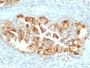

Positive Control

CAPAN-2 or HeLa cells. Lung Mesothelioma.

Mesothelioma|Ovarian cancer|Pancreatic cancer

Mesothelin is a 40 kDa glycosyl-phosphatidylinositol-anchored glycoprotein cleaved from a 69 kDa precursor protein. Mesothelin immunoreactivity is high in cancers of the ovary (serous papillary, endometrioid and undifferentiated) and pancreas, with less frequent staining seen in adenocarcinomas of the endometrium, lung and stomach/esophagus. Mesothelin is one of the most sensitive markers for mesothelioma.Primary antibodies are available purified, or with a selection of fluorescent CF® Dyes and other labels. CF® Dyes offer exceptional brightness and photostability. Note: Conjugates of blue fluorescent dyes like CF®405S and CF®405M are not recommended for detecting low abundance targets, because blue dyes have lower fluorescence and can give higher non-specific background than other dye colors.

IHC (FFPE) (verified)

Higher concentration may be required for direct detection using primary antibody conjugates than for indirect detection with secondary antibody|Immunohistology (formalin): 1-2 ug/mL for 30 minutes at RT|Staining of formalin-fixed tissues requires boiling tissue sections in 10 mM citrate buffer, pH 6.0, for 10-20 minutes followed by cooling at RT for 20 minutes|Optimal dilution for a specific application should be determined by user